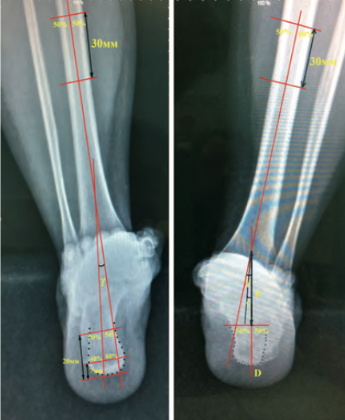

Пациенту проведено рентгенологическое исследование, по результатам которого выявлены: посттравматический остеоартроз подтаранного сустава левой стопы (3 стадия по Kellgren – Lawrence); отрицательный угол Белера, указывающий на нарушение анатомии пяточной кости; «горизонтализация» таранной кости и снижение таранно-пяточной высоты, обусловленные посттравматическими изменениями; консолидированный перелом левой пяточной кости 4 типа по Zwipp – Rammelt с фиксацией винтами и сращением фрагментов в положении смещения; консолидированный перелом малоберцовой кости, фиксированный металлоконструкцией (пластина и винты) после травмы 2002 г. Феномен «горизонтализации» таранной кости стал причиной прогрессирующего ограничения тыльного сгибания в левом голеностопном суставе, что привело к формированию переднего импиджмента в данной области (рис. 5).

В течение месяца осевая нагрузка на конечность была полностью восстановлена, что позволило пациенту вернуться к трудовой деятельности. Динамическое наблюдение за пациентом продолжали, окончательный результат лечения оценен через 12 месяцев после операции. На контрольном осмотре отмечено сохранение достигнутой коррекции заднего отдела левой стопы, отсутствие латерального пяточно-малоберцового импиджмента, восстановление угла отклонения таранной кости, угла наклона пяточной кости, угла Мири, лодыжечного роста и ширины пяточной кости (рис. 9, а). Результаты МСКТ демонстрировали консолидированный артифициальный перелом левой пяточной кости с формированием подтаранного костного блока в условиях фиксации винтами, а также консолидированный перелом малоберцовой кости в условиях фиксации блокируемой пластиной (рис. 9, б).